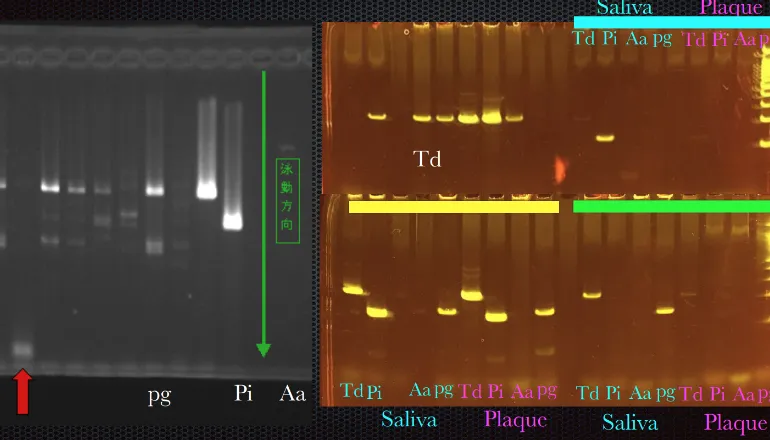

「遺伝子検査認定クリニック」です

口腔環境の菌のバランスや口内成分量など4つの検査を通して原因を特定

解析できる「遺伝子検査」

特に遺伝子検査は全国の歯科では限られた医院しか行っておらず、

位相差顕微鏡だけでは発見できない「PG菌」の検出も可能です。

慢性の歯周病患者から高頻度で顕出される菌である

PG菌のコントロールができることで歯周病を改善できます!

4つの検査

病気の元となる病原菌を解析できる「遺伝子検査」と、口腔の細菌数や内臓の健康状態を調べ、原因を特定する「ガスクロマトグラフ」。さらに「位相差顕微鏡検査」で歯周病になりやすい菌をチェックし、「唾液検査」で分泌物を調べ、組織や細胞をチェックします。